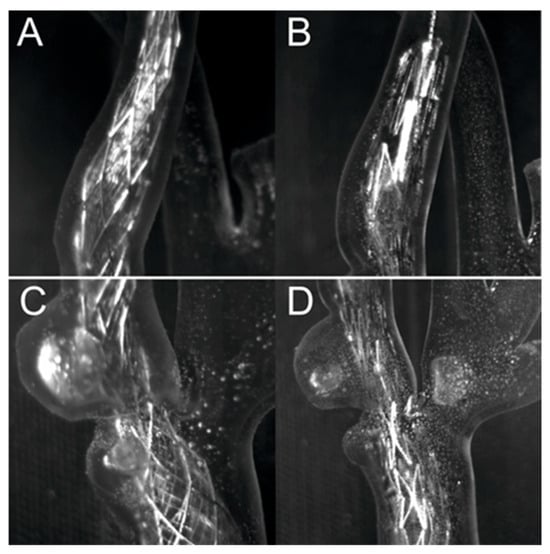

The artery models presented in Figure 8 and Figure 9 were used to assess the print quality using a solution containing rhodamine B (Figure 3b–d). The artery model shown in Figure 8 was used to compare the Roadsaver™ and Protégé™ RX stents. The deformation of the severe atherosclerotic stenosis is presented in Figure 10 using two copies of the model shown in Figure 8. Moreover, to demonstrate the deformation of the Carotid WALLSTENT™ during balloon inflation, the stent and model shown in Figure 7 were used, as shown in Figure 12. Detailed information on the stents used is presented in Table 1.

Figure 10.

Comparison of stents for two exposures, (A,C)—dense mesh (Roadsaver™—Carotid Artery Stent), (B,D)—sparse mesh (Protégé™ RX—Carotid Artery Stent).

Figure 10 shows a comparison between the Roadsaver™ and Protégé™ RX stents. Figure 10 shows two exposures for two different stent models; the first close-up shows the distal fragment of the internal carotid artery, and the second shows the fragment with the ulceration and narrowing immediately distal to the branching of the carotid artery into the internal and external carotid artery. Comparing Figure 10A,C with Figure 10B,D, it can be seen that the Protégé™ RX stent with open-cell design adapts better to the artery model wall than the Roadsaver™ stent with a mesh design.